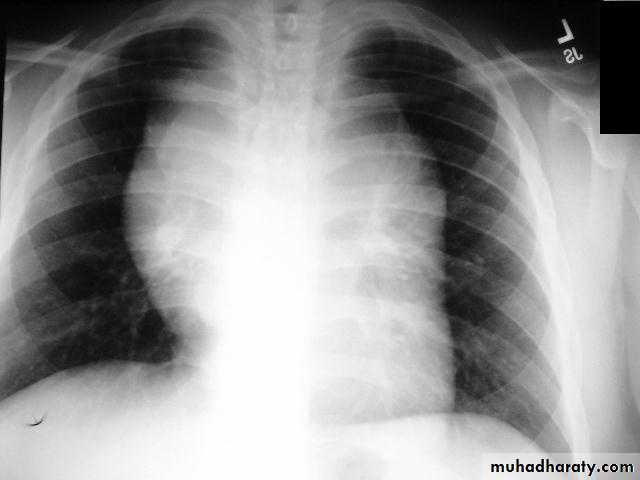

Pericardial effusions occur when fluid collects in the pericardial space (a normal pericardial sac contains approximately 30-50 mL of fluid).

Radiographic features

Plain radiograph

a very small pericardial effusion can be occult on plain film there can be globular enlargement of the cardiac shadow giving a water bottle configuration known as Globe shape heart or pumpkin shape heart

.